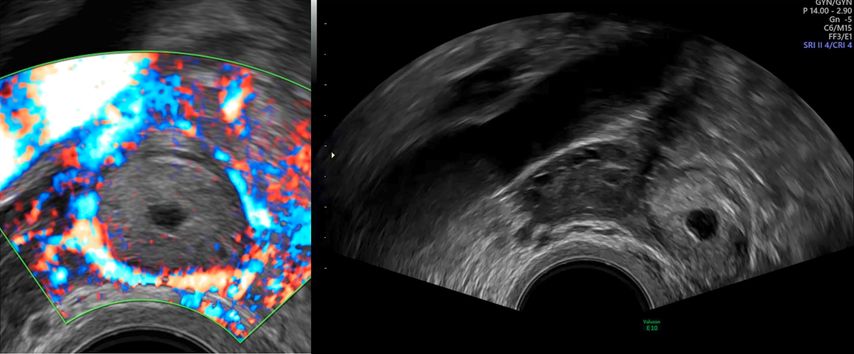

Es gibt zwei Zeichen im TVUS, die wegweisend für die Diagnostik der tubaren EUG sind. Das sogenannte «Blob-Sign» beschreibt eine inhomogene nichtzystische Masse im Bereich der Adnexloge, die sich separat vom Ovar bewegen lässt. Es lässt sich bei bis zu 60% der tubaren EUG darstellen.1 Das «Bagel-Sign» ist der zweite wegweisende Befund in der Ultraschalldiagnostik. Hierbei lässt sich eine Ringstruktur, die dem leeren Gestationssack entspricht, im Bereich der Adnexe darstellen (Abb. 1). Diese ist in ca. 20% der Fälle auffindbar. In weiteren 20% lässt sich eine embryonale Struktur darstellen. Wenn eine positive Herzaktion in der EUG nachweisbar ist, handelt es sich um eine vitale EUG.1,12